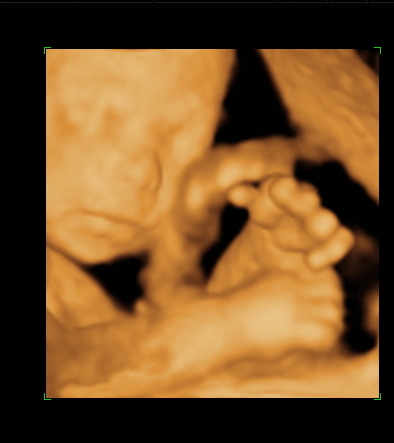

En pont ma toltottem be a 24.hetet,es mar tudjuk hogy kisfiu lesz!

A Botond nevet valasztottuk.